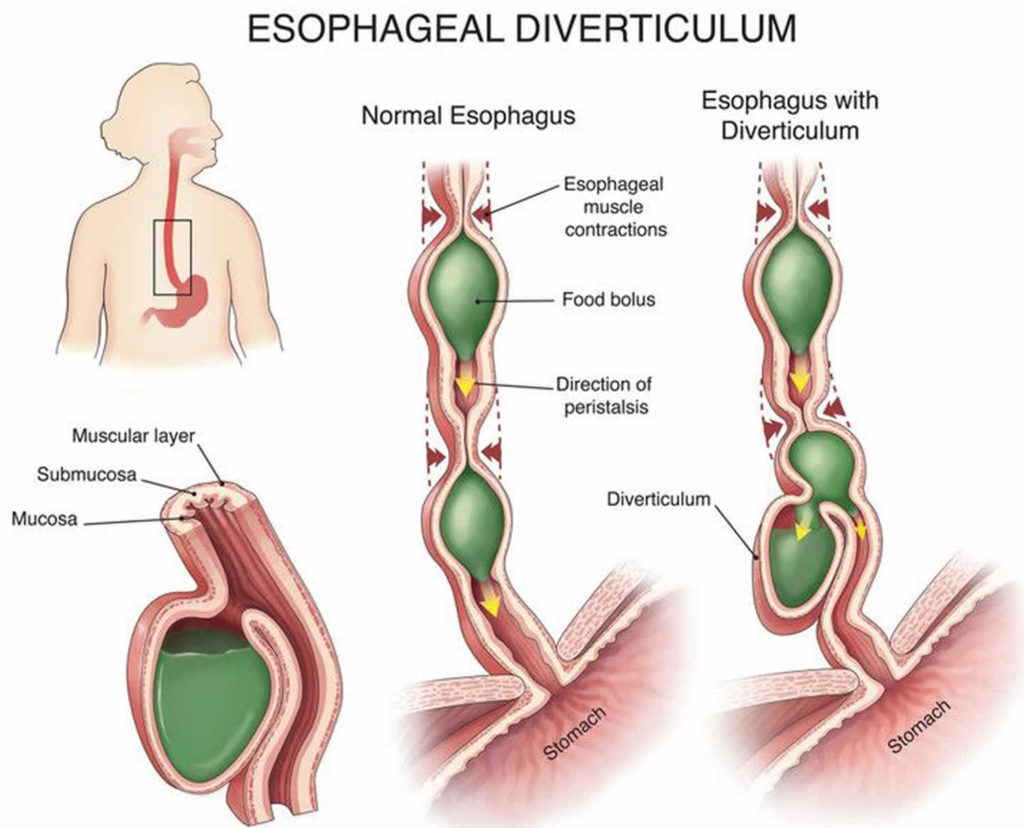

Esophageal Diverticulum Causes Types Symptoms Diagnosis Treatment